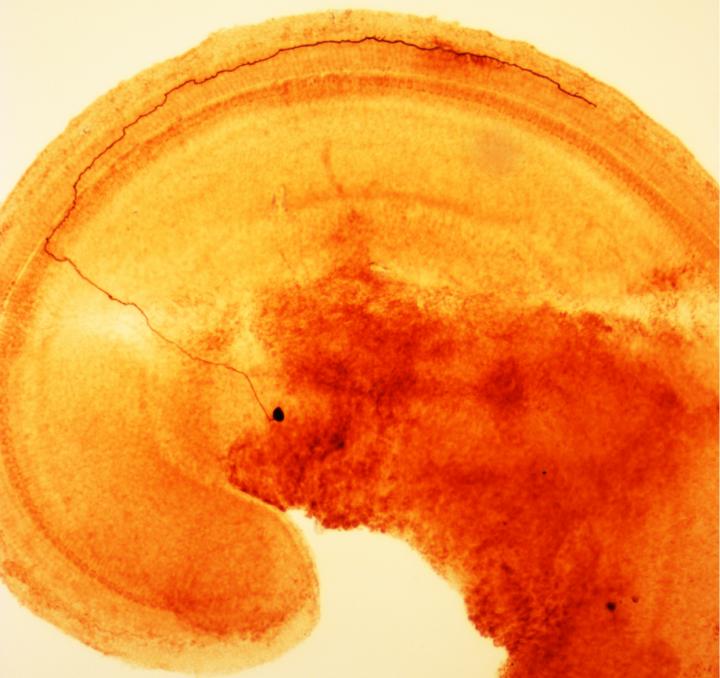

Some nerve cells in the inner ear can signal tissue damage in a way similar to pain-sensing nerve cells in the body, according to new research from Johns Hopkins. If the finding, discovered in rats, is confirmed in humans, it may lead to new insights into hyperacusis, an increased sensitivity to loud noises that can lead to severe and long-lasting ear pain.

Fuchs and his team knew that these type II afferents connect to specialized sensory cells in the ear of mammals. These so-called outer hair cells amplify the sound waves that enter the inner ear, giving mammals very sensitive hearing over a wide range of frequencies. But, according to Fuchs, this specialization comes at a cost.

"Outer hair cells are the canaries in the coal mine for the inner ear, in that they're the first cells to die due to loud noise, age or other factors," says Fuchs. "Since they can't regenerate, their death leads to permanent hearing loss." So one possible role for type II afferents, he adds, would be to warn the brain of impending damage to outer hair cells.

It was known that nearby supporting cells respond to outer hair cell damage by increasing their inner calcium levels and releasing the chemical messenger ATP. Fuchs' team knew that type II afferent neurons can respond to ATP, so they damaged outer hair cells while monitoring type II neurons in surgically removed inner ear tissue. Indeed, outer hair cell rupture caused robust excitation of type II neurons.